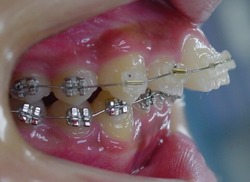

当矯正歯科医院ではMEAW法(マルチループ)で治療する事で非抜歯で治療しています。

MEAW法(マルチループ)を利用することで以下の様に上顎前突が改善されていきます。

治療途中